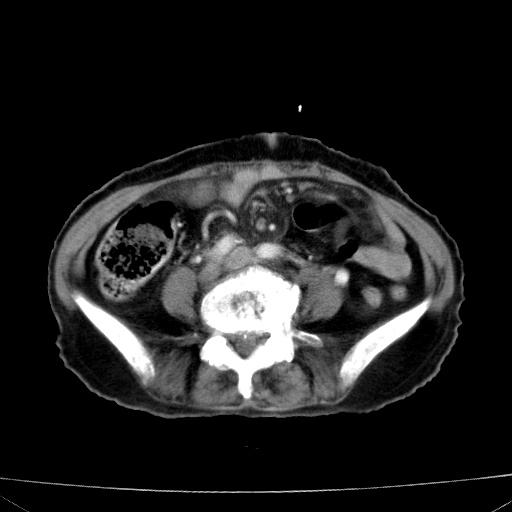

网站人气太旺!昨天的帖子就沉到海底,只好再发贴!ct18338:女 78岁,肝胆病变,已增强,再会诊!原帖链接:http://www.radida.com/bbs/forum.php?mod=viewthread&tid=50032

1)考虑胆囊癌侵犯肝脏并肝门区、腹膜后及右侧膈角后淋巴结转移。2)肝左叶近肝顶部囊肿。3)肝左叶肝内胆管结石。4)左肾近下极囊肿。

3,肾囊肿